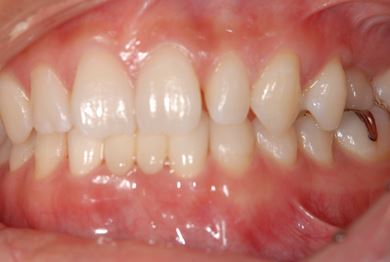

| 性別/年齢 | 女性 / 28歳 | ||||||||||||||||||||||||||||||||

| 主訴 | 下前歯の色が気になるので、ホワイトニングかセラミック治療できれいにしたい。(下前歯2本は乳歯でした) | ||||||||||||||||||||||||||||||||

| 治療方針 | 下顎前歯、乳歯を抜歯し、セラミック治療にて審美的回復を行う。 | ||||||||||||||||||||||||||||||||

| 治療内容 | エンプレスジルコニアフレームオールセラミッククラウンブリッジ4本 | ||||||||||||||||||||||||||||||||